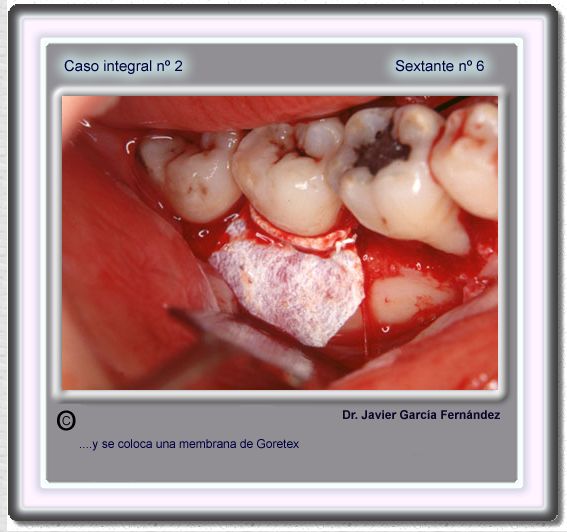

image 80